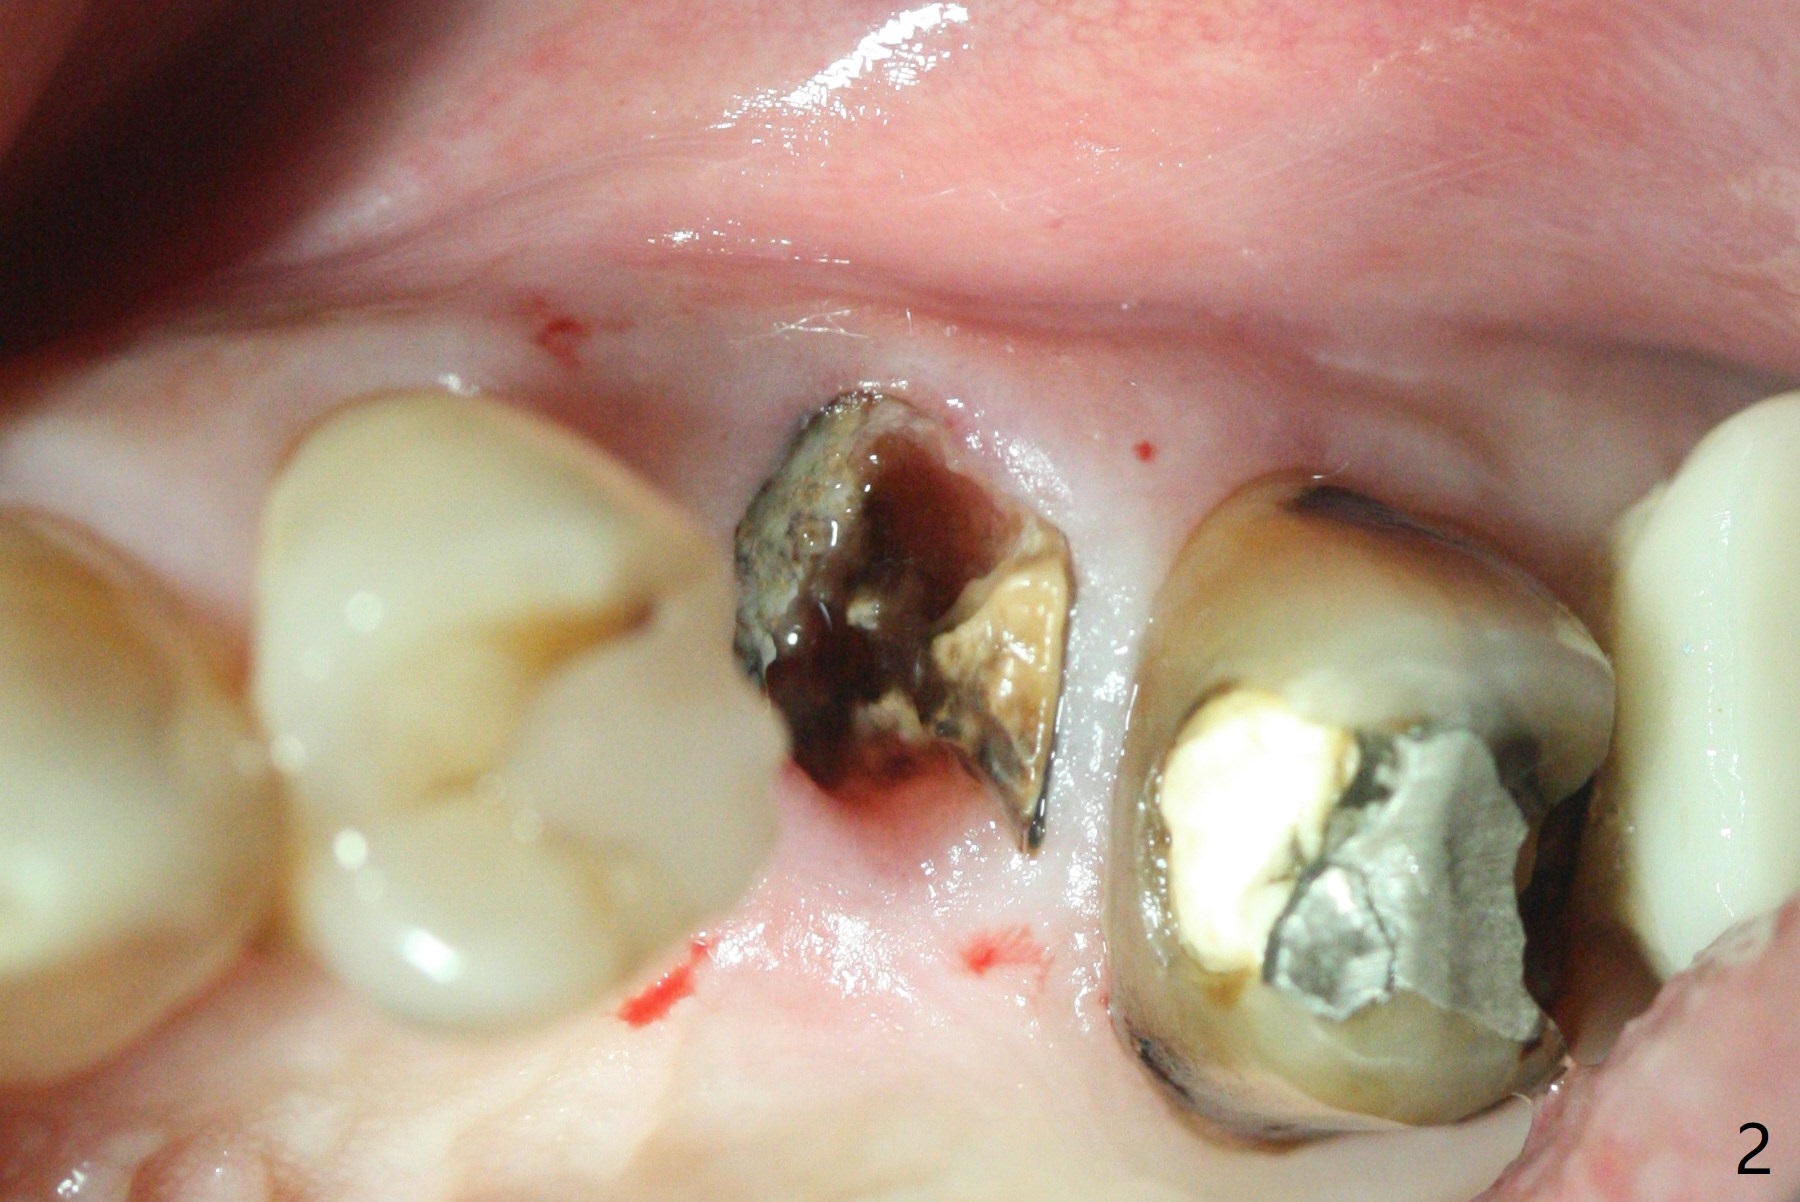

The patient with the anterior cross bite at the left lateral and canine and incipient Class V caries returns to clinic for #13 residual root extraction (Fig.1,2). There is no quality root structure (Fig.2) or space (Fig.3) for socket sheath. Two amalgam carriers of Vanilla is inserted and pushed by the 4x11 mm dummy implant for sinus lift (Fig.4 *). When the same sized final implant (4x11 mm) is placed, a 5.5 mm bone profile drill is used to trim the proximal crests (Fig.5 * sticky bone packed in the buccal and palatal gaps). In fact the implant turns when a 4.5x4(3) mm pair abutment is tightened. The implant is backed up; with a healing screw, sticky bone is placed (Fig.6 *) and then covered with a piece of PRF and a part of GEM cap. The wound is sutured with 4-0 PGA; periodontal dressing is applied. The implant is somewhat over-seated without the bone graft covering the apical end of the implant (Fig.7, as compared to Fig.4). A 4.5 mm implant should be placed. The GEM Cap appears to be absent 9 days postop, while the periodontal dressing dislodged in 1 week (Fig.8). It appears that the existing abutment at #15 is incompletely seated (Fig.3, 5.5x4(2) mm). After use of 5.5 and 6.0 mm bone profile drills, a 5x4(3) mm abutment is placed with 35 Ncm torque. In fact the bone graft coronal to the implant remains (Fig.9 *) in spite of apparent loss of the overlying PRF and GEM cap (Fig.8). After use of a 4.6 mm profile drill, a 5.5x3 mm healing abutment is placed 4.5 months postop (Fig.10). Without a provisional at #13 for ~ 4 months, there is a gap between crowns at #14 and 15 (not shown due to angulation). Impression is taken for #13 crown fabrication 5.5 months postop and for #15 crown repair (addition of porcelain for the mesial contact, Fig.11). It appears critical for a provisional to maintain the position of the neighboring tooth.